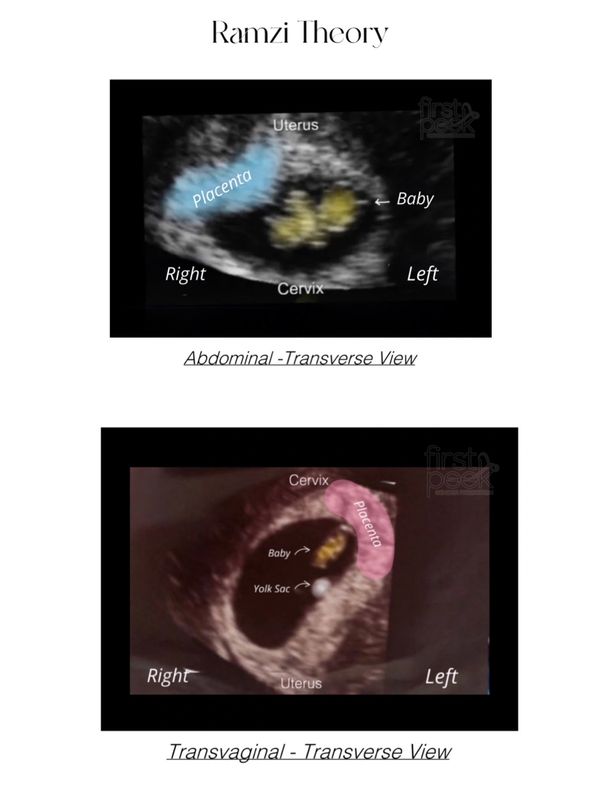

The ramzi theory was created by a a man named Dr. Saam Ramzi Ismail.

There was a study of 5,376 women that had ultrasounds starting at 6 weeks of pregnancy. During this study they found that 97.2% of male fetuses had placenta forming on the right and 97.5% of female fetuses had placenta forming on the left.

This study was not published and confirmed by other researchers. Due to this information this theory should only be used for fun on early pregnancy ultrasounds as there is not a lot of scientific information confirming that this theory holds true accuracy at predicting your baby’s gender.

The Ramzi Theory can only be used if your ultrasound was taken in the transverse view. We can only know if your scan was not taken in this view if it states it on your ultrasound such as (SAG, SAG Uterus, Saggital) so when sending your ultrasound we use it as if it were taken in the transverse view unless stated otherwise.

This can also play a part in the accuracy as well.In the transverse view the right of your ultrasound is your left and the left of your ultrasound is your right no matter if taken transvaginal/abdominal contrary to popular belief.

The gestation for this theory is 6 weeks 0 days to 8 week 5 days. What we are looking for can change locations outside of times stated above causing the theory to be inaccurate to use.